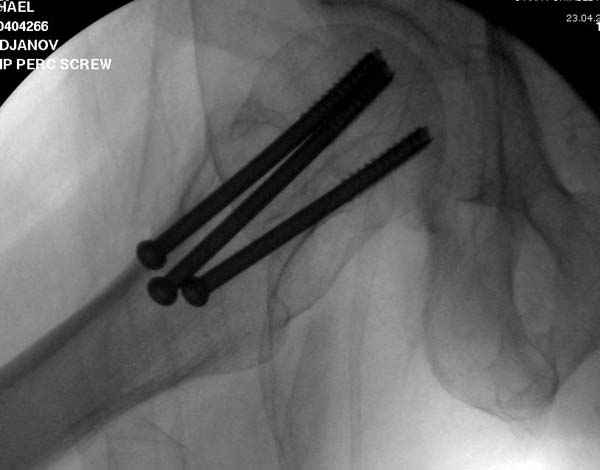

Re: неполный перелом шейки

Профилактику дальнейшего раскола неполного перелома шейки провели тремя канюлированными шурупами.

На второй день после выписки упал дома. Снимки приложены. Коллеги рекомендуют удаление шурупа и вытяжение. Что делать?